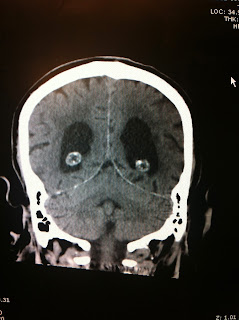

It started off with this one...

I copied the image of a brain bleed to show during a slide presentation

and realized that it looked like a sad panda

having a really bad day...